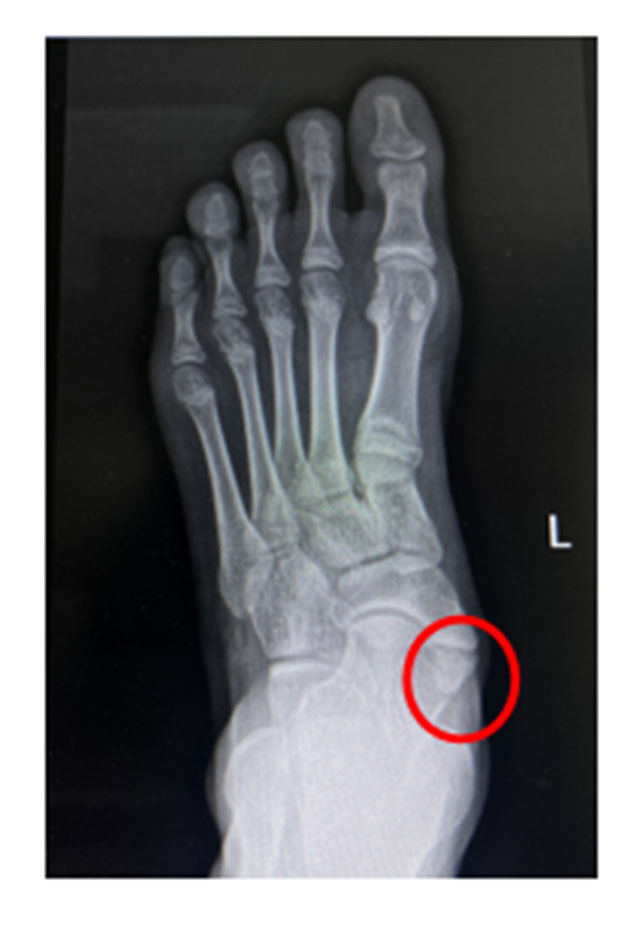

1月中旬,初中生小丽(化名)与家人一起来西南医科大学附属中医医院骨伤科关节·足踝组就诊。张磊博士接诊后了解到,小丽因最近备战体考加强了体育锻炼,但发现足内侧凸起,走路、运动都会发痛。经过专业查体和检查后,张磊博士为其诊断为“左足副舟骨痛综合...